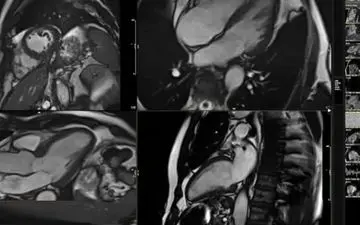

ابزار جدیدی که با هوش مصنوعی کار میکند، میتواند به شما بگوید قلب شما عمر کرده است.